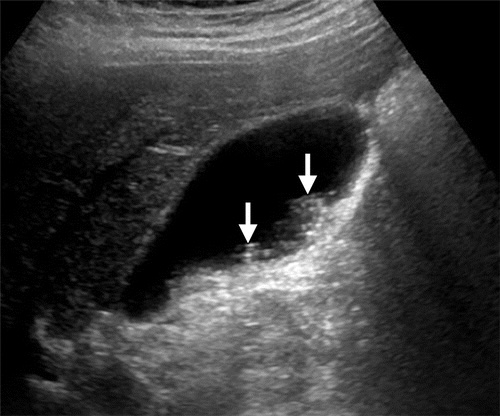

УЗИ выявляет следующие анатомические признаки:

В серошкальном режиме определяется увеличение размеров поджелудочной железы с нарушением её нормальной эхоструктуры и появлением гипоэхогенных участков.

В серошкальном режиме визуализируются жидкостные скопления в забрюшинной клетчатке с возможными признаками эхогенных включений при инфицировании.

В В-режиме возможно выявление образования капсулы вокруг жидкостных скоплений при их организации.